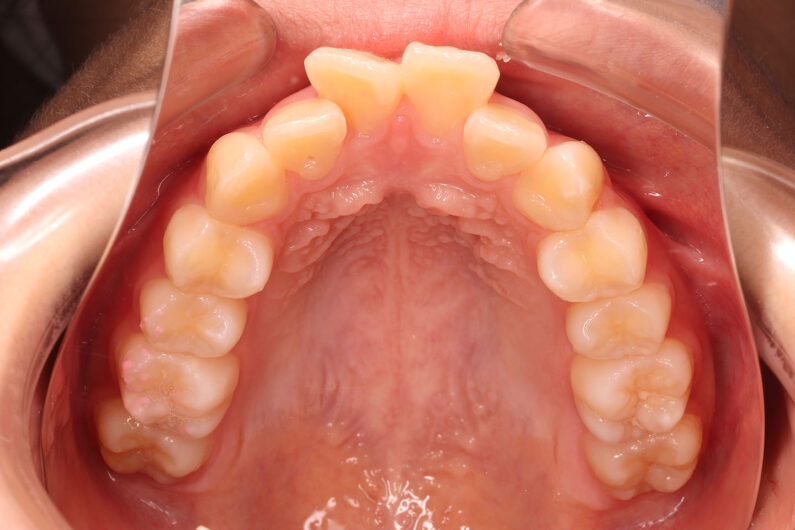

他院から紹介の患者さんです。 前歯、下の歯のガタツキをきれいにしたいということで治療を決断されました。

上顎前歯6mm、下顎前歯2.5mmの前突の状態で、口唇も前突しています。 小臼歯抜歯したスペースを使い、叢生(がたつき)と前突した前歯の後退を目標にしました。 この方も希望により、アンカースクリューは使用せず、通常の顎間ゴムで対処してもらいました。